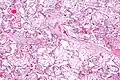

| Micrograph of villous immaturity. H&E stain. | |

Placental villous immaturity is chorionic villous development that is inappropriate for the gestational age.

Immature chorionic villi are larger and have more central blood vessels; thus, the diffusion distance for gas and nutrient exchange is larger and, therefore, placental function is impaired.